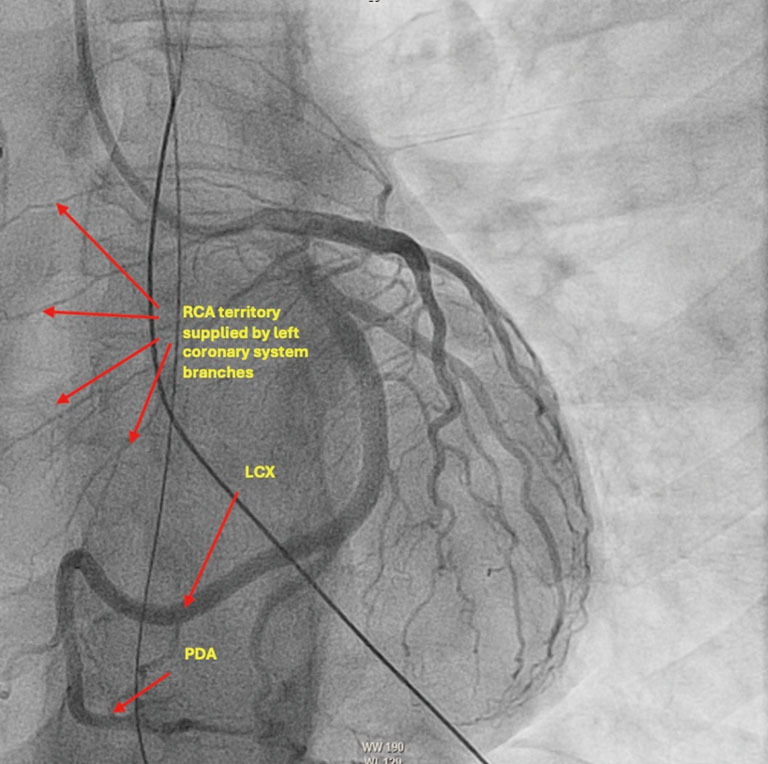

Case description: This report describes a 36-year-old female without prior cardiac history who presented in ventricular fibrillation (VF) electrical storm. While she lacked significant electrolyte abnormalities or ischemia to explain etiology of electrical storm, she incidentally had variant coronary anatomy noted on angiography. After thorough consideration of possible etiologies of storm, selective serotonin reuptake inhibitor (SSRI) intoxication was the most highly suspected etiology. Regarding management of her hemodynamically unstable electrical storm, she was treated with lidocaine, amiodarone, as well as mechanical circulatory support devices including extracorporeal membrane oxygenation (ECMO) and intra-aortic balloon pump (IABP). The patient ultimately was decannulated from ECMO, had IABP removal, and achieved recovery of ejection fraction (EF) to baseline. She was not offered ICD as the etiology of her cardiac arrest was reversable. She was discharged with recommendation to discontinue SSRI and follow up with psychiatry regarding SSRI overdose.